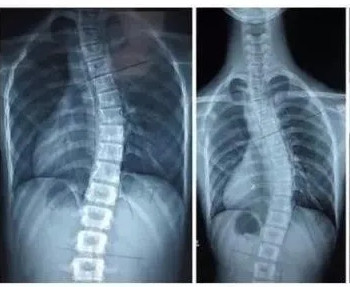

脊柱側(cè)彎是一種脊柱的三維畸形,在失狀面,冠狀面,橫斷面上的序列均會產(chǎn)生異常。在X光檢查中如果顯示脊柱有10度以上的側(cè)方彎曲,即會診斷為脊柱側(cè)彎。